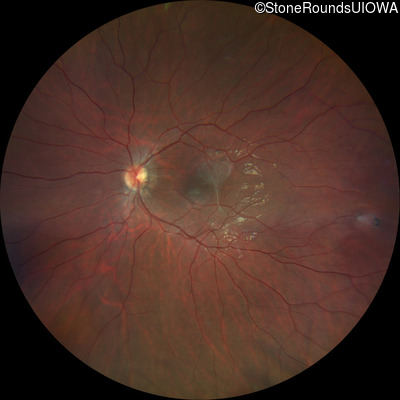

This 9 year old male was noted to have some crossing of his eyes at 2 months of age and the eye exam which followed identified a retinal lesion in the right eye. When he was six years old an epiretinal membrane was noted in his left eye. Two years later it was decided that it was a thin hamartoma in that eye as well. He underwent neuroimaging at age 7 which identified bilateral acoustic neuromas.

| Age at visit: 8 years |

| Age at visit: 10 years |

| Age at visit: 11 years |

| Neurofibromatosis | NF2 | Trp258 del1tG | AD |